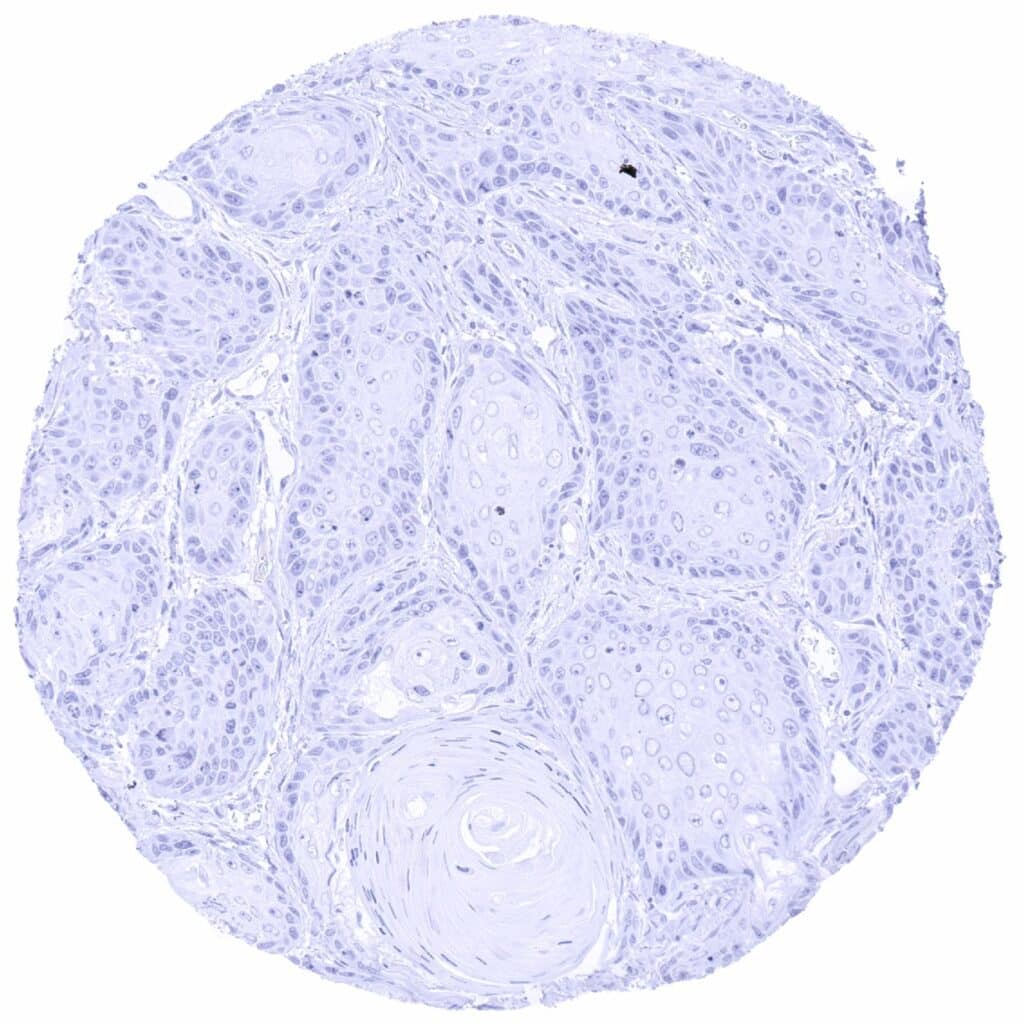

Uterus, cervix – Pax6 negative squamous cell carcinoma